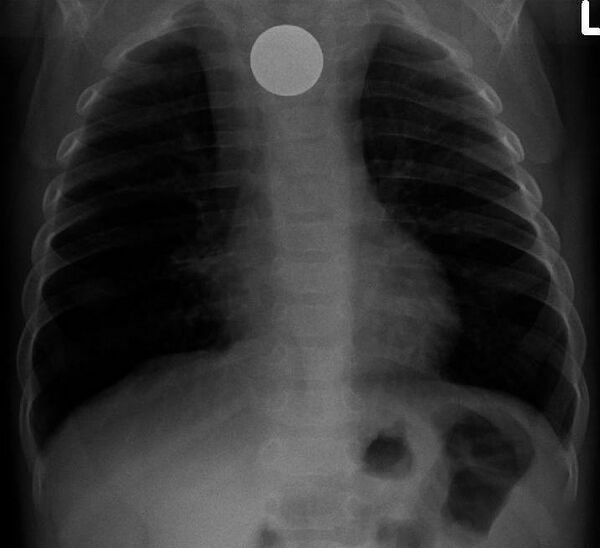

Инородные тела ЖКТ

Одна из распространённых локализаций инородных тел — желудочно-кишечный тракт. Возможные пути проникновения инородных тел — ротовая полость[13] или прямая кишка[14]. Дети чаще проглатывают монеты[15], у взрослых в 75 % случаев инородными телами служили мясные кости[16].

Наиболее часто проглоченные предметы обнаруживают в пищеводе или желудке, реже в глотке или двенадцатиперстной кишке[17].